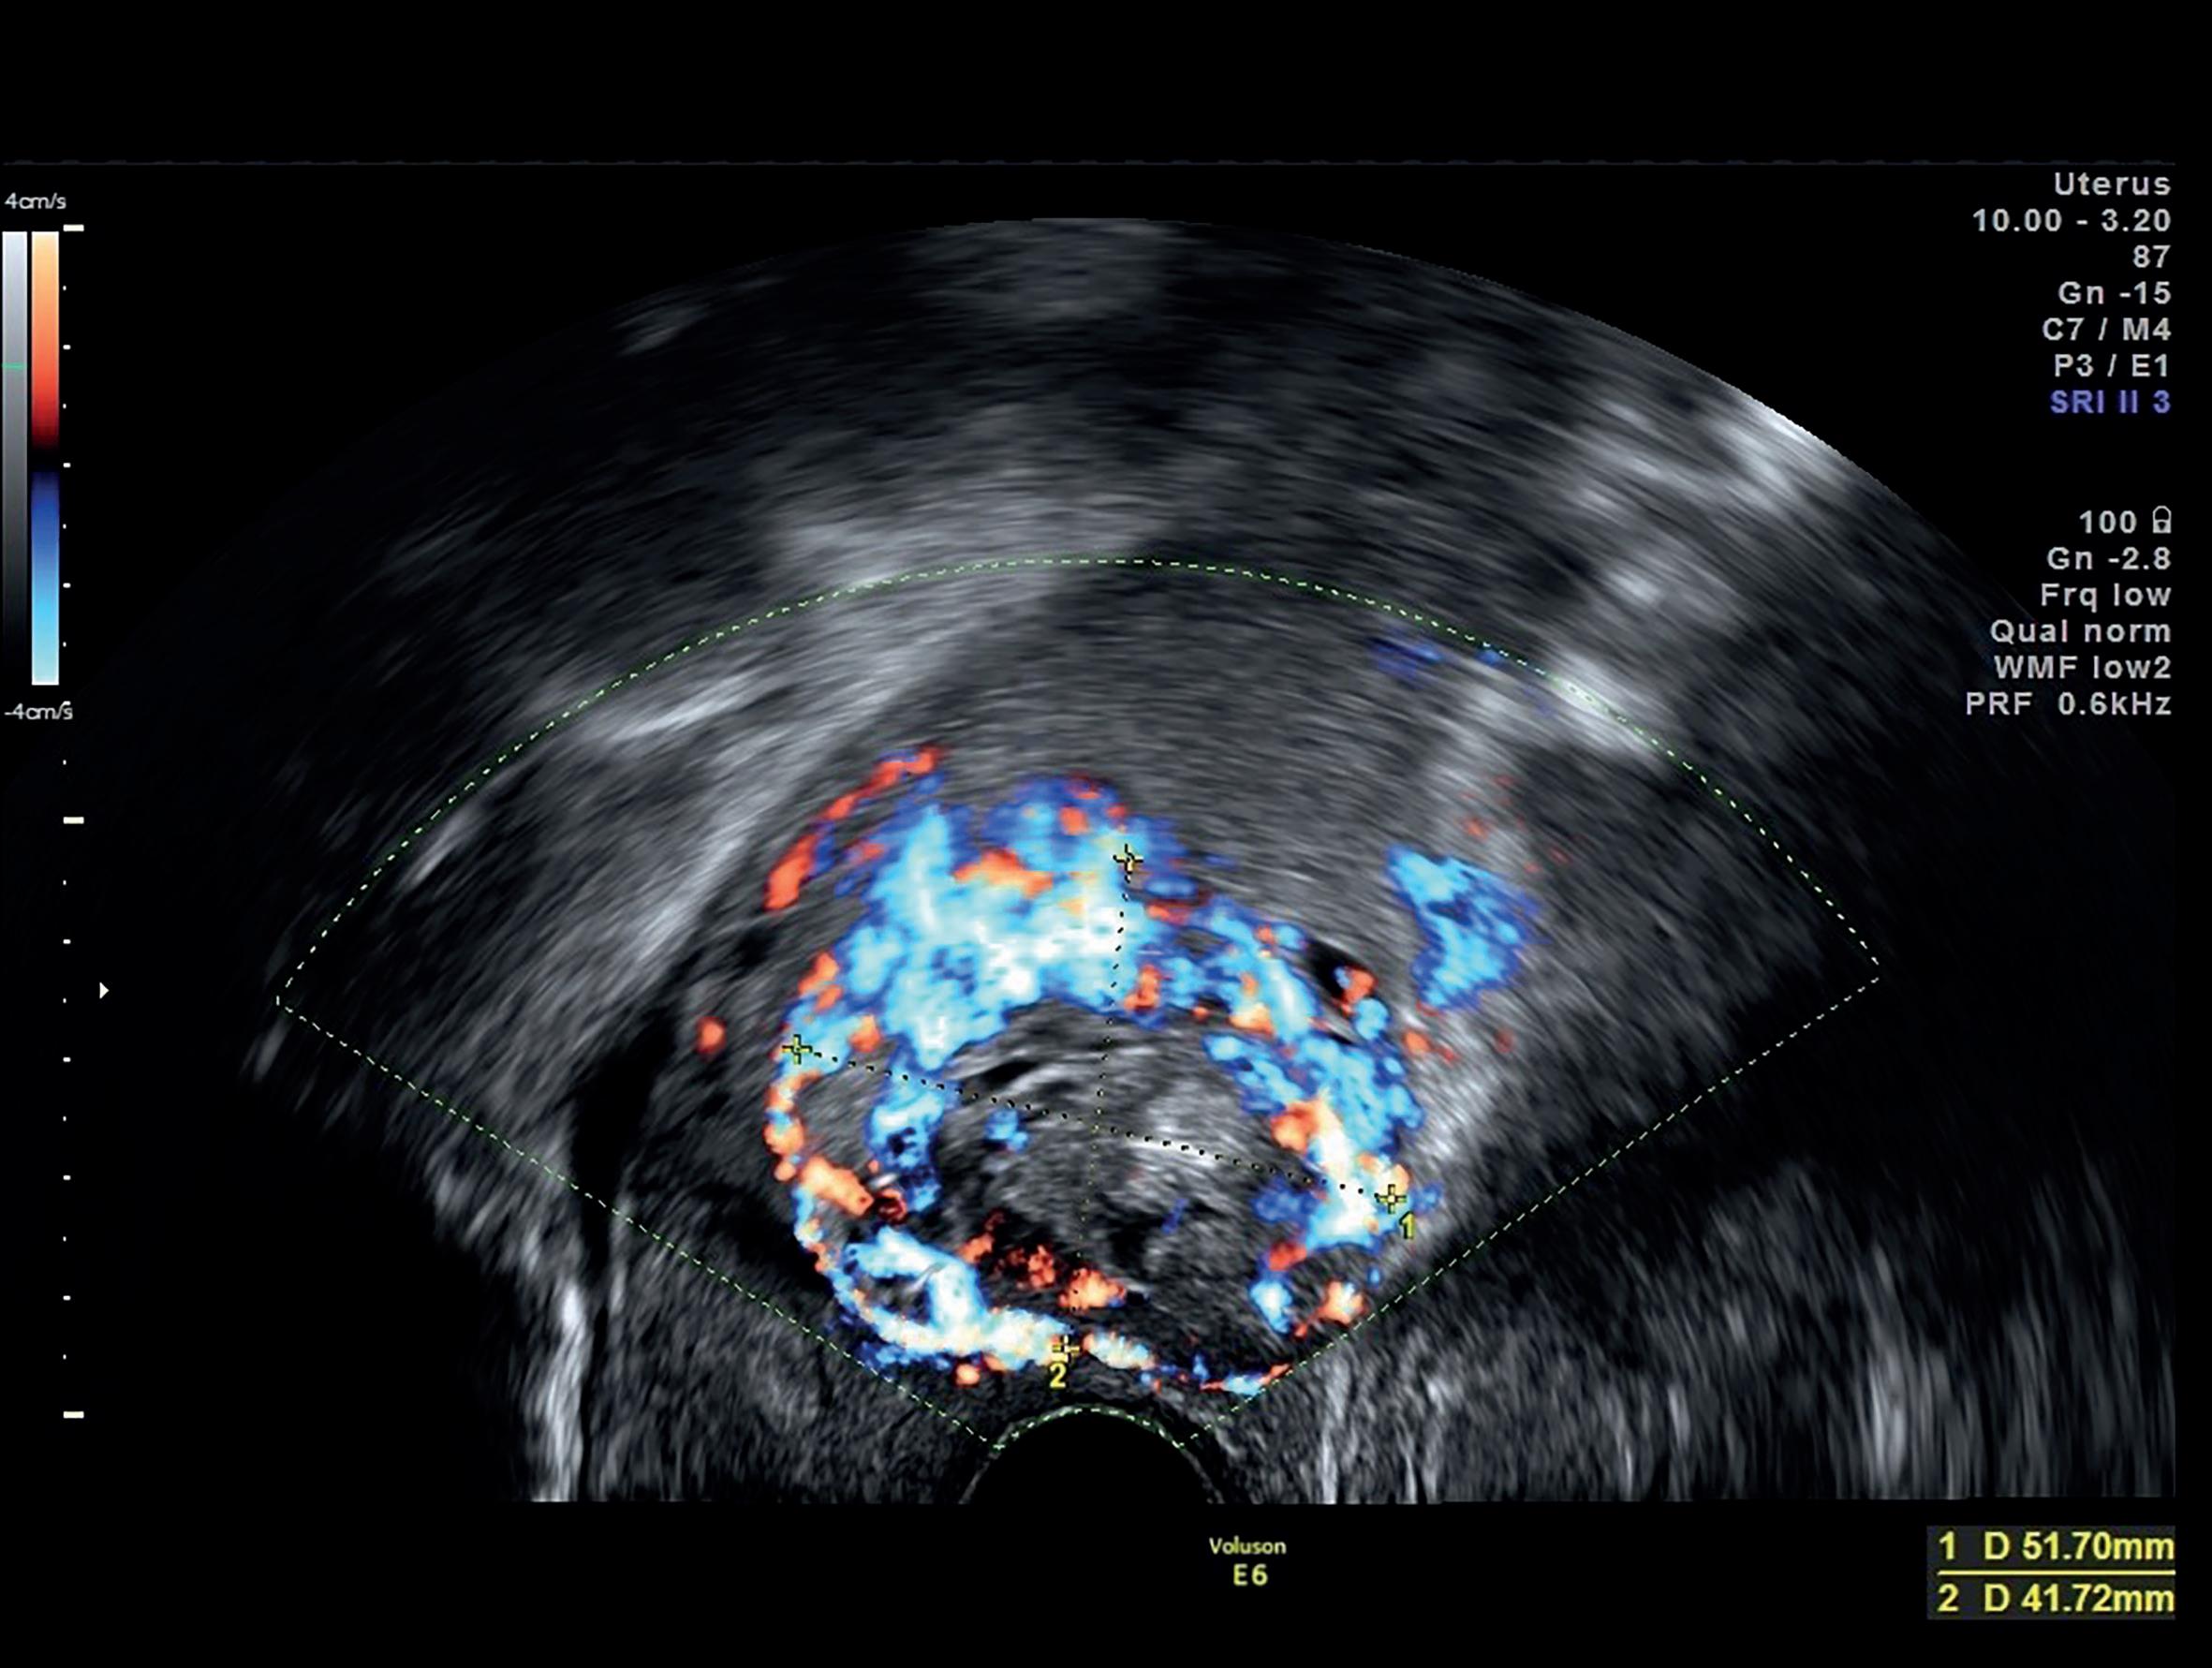

■ Hipervascularização peritrofoblástica com fluxo de alta velocidade (>20 cm/s) e baixa impedância (IP <1) (Figura 28.5).

Figura 28.5 – Gravidez ectópica em cicatriz de cesariana – hipervascularização peritrofoblástica. (Fonte: ULS São João)